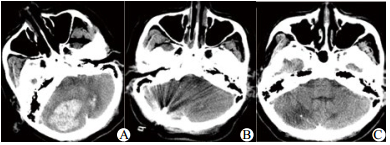

3.4 典型病例患者女,60岁零9个月,因“神志不清、呕吐、抽搐3 h”于2014年1月15日急诊入院。患者有高血压病史多年,服用硝苯地平缓释片控制血压,血压控制不详。有精神分裂症史。入急诊室时生命体征BP 220/140mmHg, P 62次/min, R14次/min, SaO2 90%, GCS评分5分,双侧瞳孔等大等圆,直径2 mm,光反射迟钝。立即给予气管插管,急诊头颅CT(图 1)示:①小脑出血(出血量约19 mL); ②梗阻性脑积水,拟“①高血压并小脑出血; ②高血压病3级,极高危; ③梗阻性脑积水”; 收住EICU病房。局麻下用YL-1型颅内血肿穿刺针行右侧脑室穿刺引流,缓解颅内高压。之后送CT室行小脑血肿定位,采用YL-1型颅内血肿穿刺+尿激酶液化术,手术顺利,清除血肿约10 mL, 术后予脱水降颅压、监控血压、抗感染、营养神经、亚低温、镇痛镇静对症支持治疗,4 d后患者神志转清,GCS12分,复查头颅CT, 小脑血肿基本清除,拔除颅内穿刺针。患者自主呼吸平稳,拔除气管插管,7 d后转普通病房治疗。随访3个月,GCS评分15分, 可缓慢步行,左侧肢体肌力5级,右侧肢体肌力4级, ADL-Barthel指数评定65分。

| A:术前,小脑出血约19 mL, 小脑实质、脑干受压,脑干周围池显示不清;B:术后1 d, YL-1型颅内血肿穿刺+尿激酶液化术后,小脑出血较前减少;C:术后1月,右侧小脑半球见片状低密度影,脑干环池结构恢复 图 1 女性患者头颅CT片 Figure 1 The CT picture of the female patients |